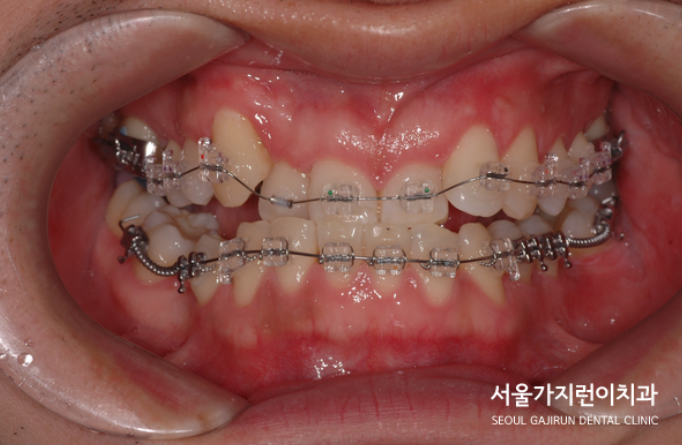

전치의 교차교합과 턱뼈의 비대칭, 주걱턱의 개선을 위해 잇몸뼈에 미니스크류를 식립한 것도 사진으로 남겼습니다. 치아교정 과정은 이런 식으로 진행이 되었으며 교정치료를 시작한 지 33개월 만에 장치를 제거하게 되었는데요. 긴 교정기간이었지만 환자의 입장에서 비수술로 치아교정을 마칠 수 있게 되어 만족도가 높았던 케이스였습니다.